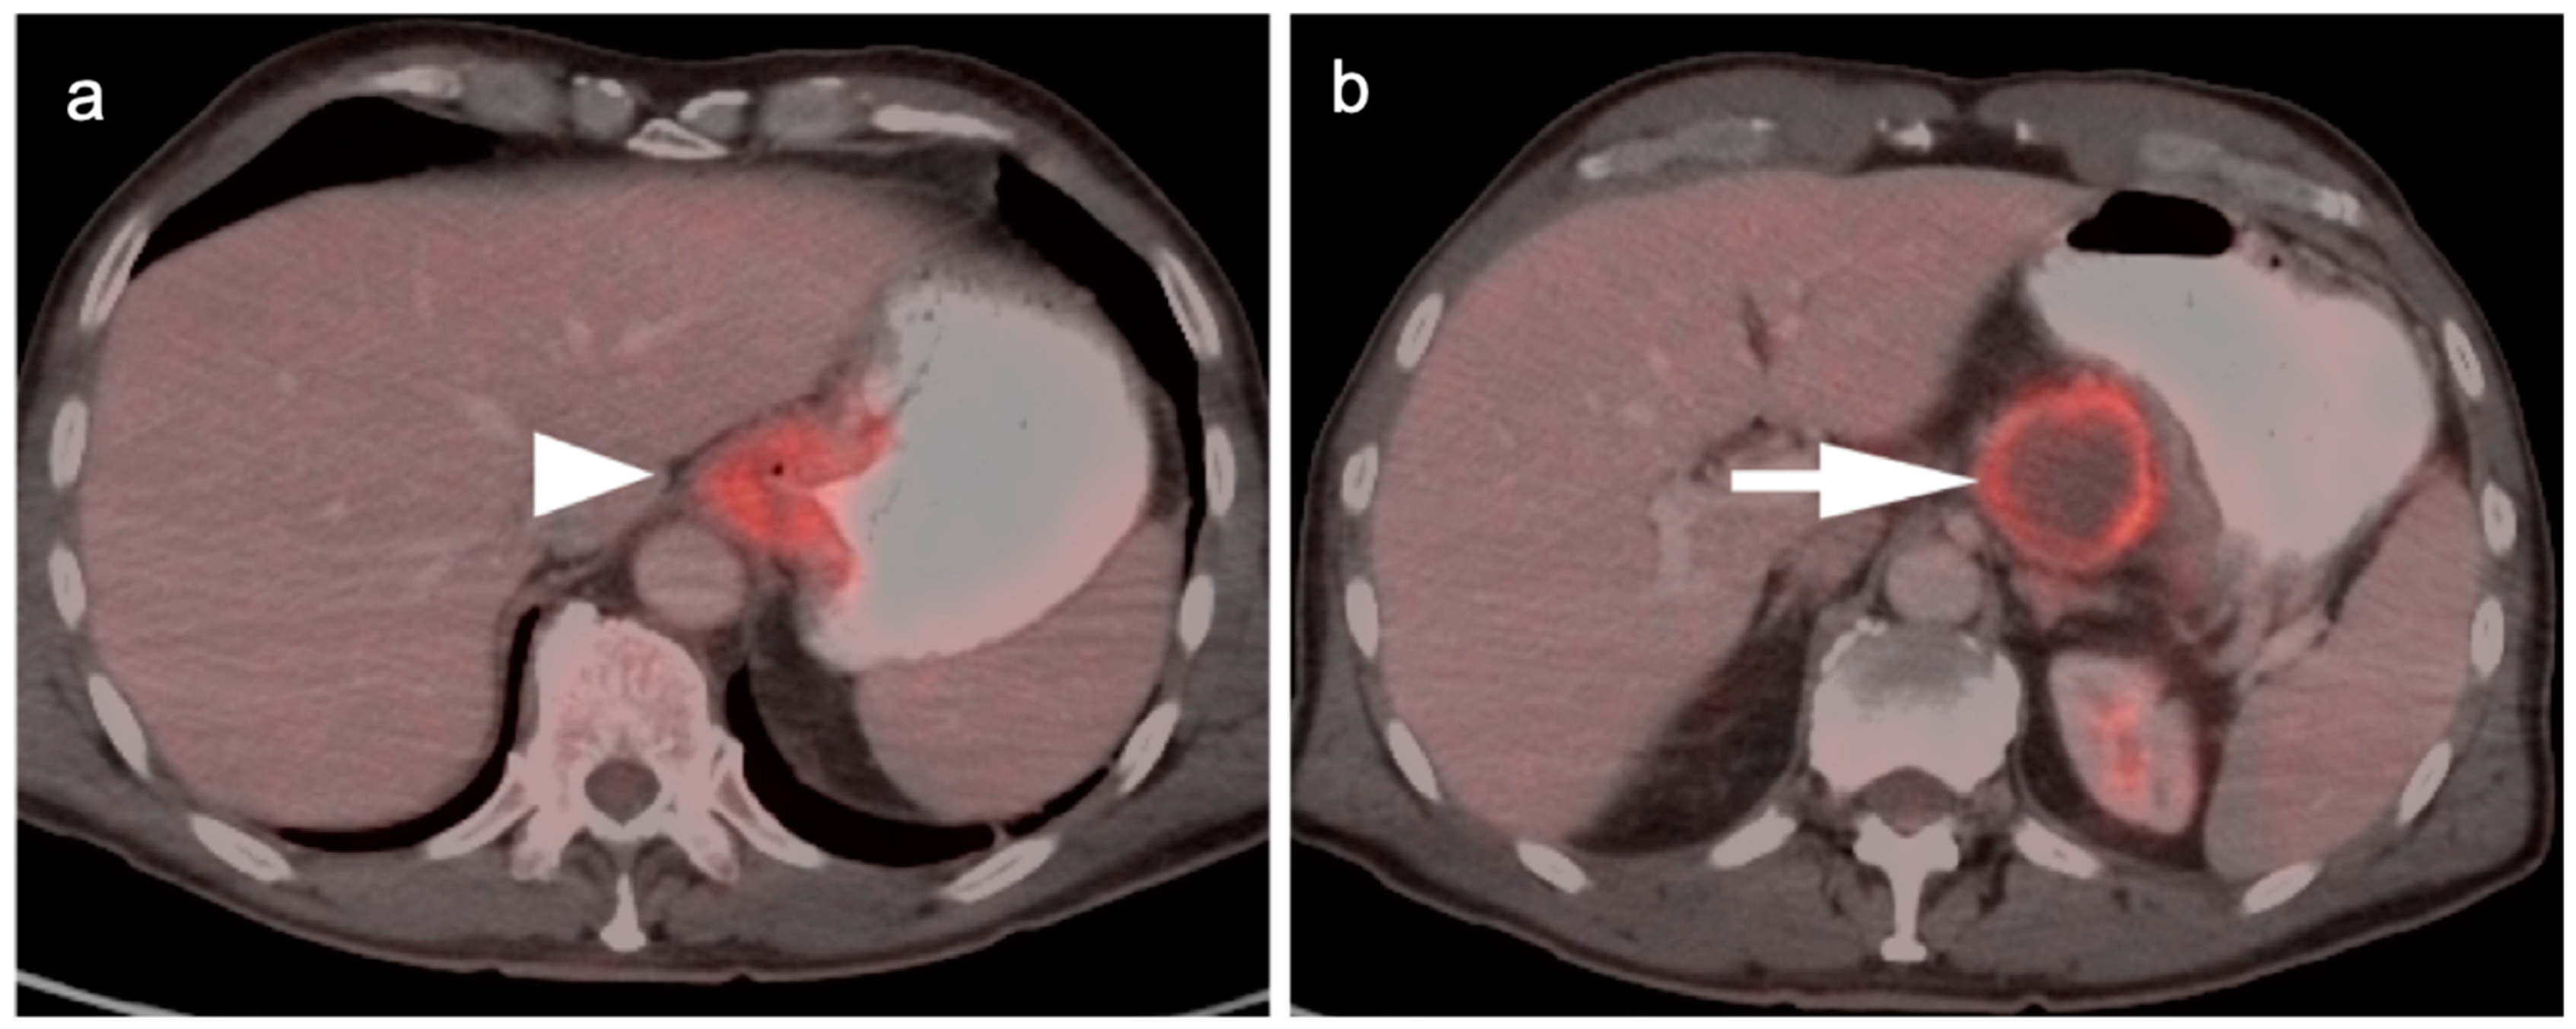

4. Hepatocellular Carcinoma